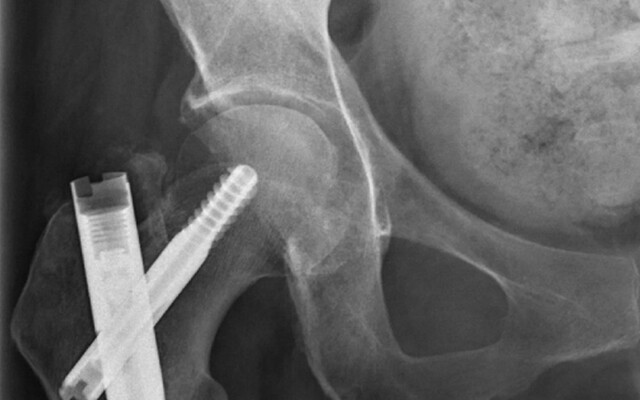

Fracturen komen in Nederland heel veel voor. Jaarlijks komen in Nederland meer dan 130.000 personen van 50 jaar en ouder naar de SEH met een fractuur.1 Het fractuurrisico neemt toe met de leeftijd, met als belangrijkste oorzaken osteoporose, frequent vallen en comorbiditeit. Mensen met een hoog fractuurrisico ervaren geen klachten. Daardoor is vaak sprake van onderdiagnostiek en onderbehandeling; vaak wordt het hoge fractuurrisico pas vastgesteld wanneer de patiënt een fractuur heeft doorgemaakt.

Osteoporose is een chronische aandoening die voornamelijk voorkomt op oudere leeftijd, met name bij vrouwen. De aandoening wordt gekenmerkt door een verlaagde botdichtheid en een veranderde microarchitectuur…